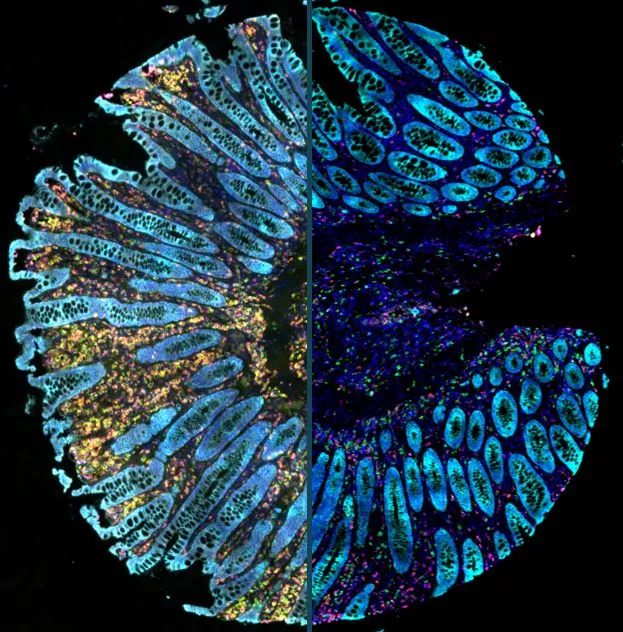

New StrataQuest App: IF ARTIFICIAL SKIN

The IF Artificial Skin App stratifies skin equivalents into dermis and epidermis, further dividing the epidermis into stratum corneum, suprabasal, and basal layers. It outputs area, mean staining intensity, nuclei counts, and % of marker-positive cells for each layer and sublayer. Read publication here